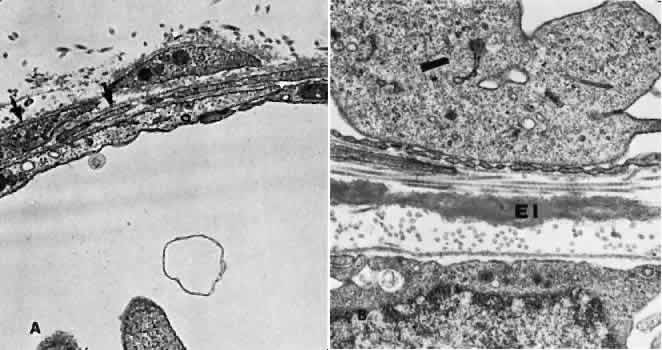

In the retrolaminar zone, the contribution of the choroidal vessels is less. The peripheral aspects of the postlaminar optic nerve are supplied by the pial vessels, whereas the central portion is fed by the axial vessels off the CRA. The afferent channels derived from the short PCAs that cross the border tissue of Elschnig at the level of the choroid have a diameter ranging from 10 to 17 μm.36,37 They quickly branch into a tridimensional vascular network with a polygonal capillary bed. The capillary bed is nonfenestrated, with tight junctions. Numerous pericytes surround the endothelial cells. The capillary mesh measures from30 × 50 μm to 50 × 80 μm, and there are multiple arterial feeding points into the meshwork. The density of the meshwork seems equal in all disc quadrants. Although the capillary bed of the optic nerve head is derived mostly from posterior ciliary vessels, it more closely resembles the retinal capillary bed morphologically than the choriocapillaris. The major efferent vessel for this area of the optic nerve is the CRV. Some of the prelaminar drainage may be through the choroid as well. Direct communications between the CRV and choroidal veins may exist as a result of CRV obstruction or as anatomical variants, which would make the eventual drainage system the vortex veins. The surface capillaries of the optic disc are derived from the retinal vessels.35,37 They anastomose with capillaries of the retina. The prelaminar, choroidal-derived vessels may contribute somewhat to the surface capillary supply. The postcapillary venules that drain the RPC system cross over the disc margin to join with larger venules of the CRV system. It may be these terminal endings of the RPC that bleed with papilledema and other causes of disc swelling. The blood flow to the optic nerve head appears to be under local autoregulatory control.38–40 This flow pattern is similar to the retinal circulation. The site of the autoregulation is not clear; however, both endothelial cells and pericytes probably have a role. The clinical appearance of optic nerve blood vessels in various pathologic conditions has been the focus of intense interest. Alterations in optic nerve blood vessels associated with advancing glaucoma have been an area of particular study in light of the theories concerning a vascular origin for the disease. Quigley and colleagues41 noted that the density of optic nerve head capillaries did not appear to change with worsening glaucoma and that eventual loss of capillaries was in proportion to the accompanying loss of neural tissue. Jonas and associates42 showed that the diameter of parapapillary retinal blood vessels was smaller in eyes with advanced glaucoma than in eyes without glaucomatous damage. This finding appears to represent an autoregulatory response of the retinal and optic disc vasculature to the local loss of retinal ganglion cells and nerve fiber layer. This study confirms an earlier report showing a significant decrease of RBF to the retina in eyes that had undergone inner retinal degeneration.43 CHOROID The choroid is by far the most vascular portion of the eye and by weight is one of the most vascular tissues in the body.44 More than 80% of all ocular blood flow goes to the choroid. The choroidal circulation is responsible for the nourishment of the photoreceptor/retinal pigment epithelium (RPE) complex. Despite these facts, the choroidal circulation has received relatively little attention for two reasons. First, it is difficult to visualize the choroidal vessels directly, and second, there are relatively few pathologic conditions that have unequivocally been associated with a primary deficiency in choroidal circulation. Choroidal blood flow can be assessed in a qualitative manner with fluorescein angiography. The rapidity of choroidal filling, the normal permeability of the choriocapillaris, and the normal blockage of fluorescence as a result of the RPE impede the identification of choroidal perfusion defects. When present, the clinical significance of choroidal perfusion defects on fluorescein angiography is not always clear, either. Newer methods used to study choroidal perfusion more quantitatively include indocyanine green angiography and color Doppler ultrasonography.45,46 Indocyanine green angiography in particular has made the choroid more accessible to clinical evaluation and interpreting the role of the choroid in various disease entities. Along with its paramount task of providing nutrition to the outer retina and RPE, the choroidal circulation also has other roles. It serves as a heat sink, removing the large amount of heat that develops as a result of the metabolic processes initiated when photons strike the photopigments and RPE.47 In addition, the choroid itself probably serves as a mechanical cushion for the internal structures of the eye. The overall structure of the choroidal circulation is segmental.47–52 This segmental distribution of blood begins at the level of the posterior ciliary branches and is mirrored in the vortex vein drainage system. Because of the segmental distribution, the large and medium-sized choroidal arteries act as end arteries. Unlike most other tissues, in the choroid the large vessels do not run parallel to each other. The segmental distribution of blood flow to the choriocapillaris is reflected in certain disease states, such as malignant hypertension. Each terminal choroidal artery supplies an independent lobule of choroidal capillaries (Figs. 11 and 12). Examination of the lobular structure reveals that feeding arterioles are usually found in the lobule center with draining venules located at the lobular periphery, but reversals of this pattern are frequently seen. There is little or no functional communication between adjacent capillary lobules.53–56 The vasculature of the choroid appears to be under direct adrenergic innervation.13,57 It is hypothesized that the parasympathetic innervation is through the seventh cranial nerve by way of the pterygopalatine ganglion.58 Arteries and Arterioles Within the choroid, the arteries and arterioles lie in stratified layers, with the larger vessels located in the outermost layer. The innermost layer of choroidal vessels is a single layer of capillaries. The arteries of the choroid measure between 20 and 90 μm in diameter.59 The larger vessels contain an endothelium and basement membrane, an internal elastic membrane, and a single continuous layer of smooth muscle cells. The muscle cells contain abundant myofilaments, and pinocytotic vesicles are arranged along the inner surface of the plasma membrane. The adventitia is composed of bundles of collagen fibers, scattered elastic fibers, and occasional fibroblasts. In the smaller vessels (arterioles), the internal elastic membrane disappears, and the muscle layer becomes discontinuous and more circumferentially arranged. The collagen present in the adventitia also becomes considerably diminished. Veins and Venules The choroidal veins that directly feed the vortex veins have a diameter less than 150 μm.59 The veins with a diameter between 50 and 150 μm have an endothelium and basement membrane with one or two layers of smooth muscle and a relatively thick collagenous adventitia. In the venules (smaller than 40 μm), the intima is the same, but the media contains a discontinuous layer of longitudinally arranged pericytes. Choriocapillaris The choriocapillaris is the unique capillary system of the choroid. The vessels of the choriocapillaris are unusual because of their large diameters. The lumina are typically larger than 8 μm. Lumina of this size allow passage of multiple red blood cells at any moment in time. The choriocapillaris is arranged in a specific lobular pattern to ensure maximum exposure of the overlying outer retina/RPE complex. Each lobule acts as an independent vascular system with its own afferent and efferent vessels.60 Within the posterior pole region, there are more venules than arterioles, probably to allow rapid flow. Other local variations exist. The lobules at the posterior pole are 200 to 400 μm in diameter and gradually enlarge to 1,500 μm in the periphery and somewhat lose their lobular pattern (Fig. 13).54,61 The vessel walls themselves consist of fenestrated endothelium surrounded by a basement membrane and a sparsely arranged layer of pericytes. The portion of the endothelial cell containing the nucleus also contains most of the cell's cytoplasm and organelles. The remainder of the cytoplasm is extremely attenuated, and these regions contain the fenestrae. These fenestrae are approximately 700 to 800 nm in diameter and are covered by a diaphragm. The attenuated areas are most typically found facing the RPE and contain very few pinocytotic vesicles. The region of the cell facing the suprachoroidal space usually contains more cytoplasm, fewer fenestrae, and the nucleus (Fig. 14). Few pericytic processes are seen in cross sections of these vessels on the side of the vessel facing the pigmented epithelium (Fig. 15). However, these processes are more numerous on the surface of the vessel facing the sclera. Because of the fenestrae, the choriocapillaris actively leaks fluorescein molecules.